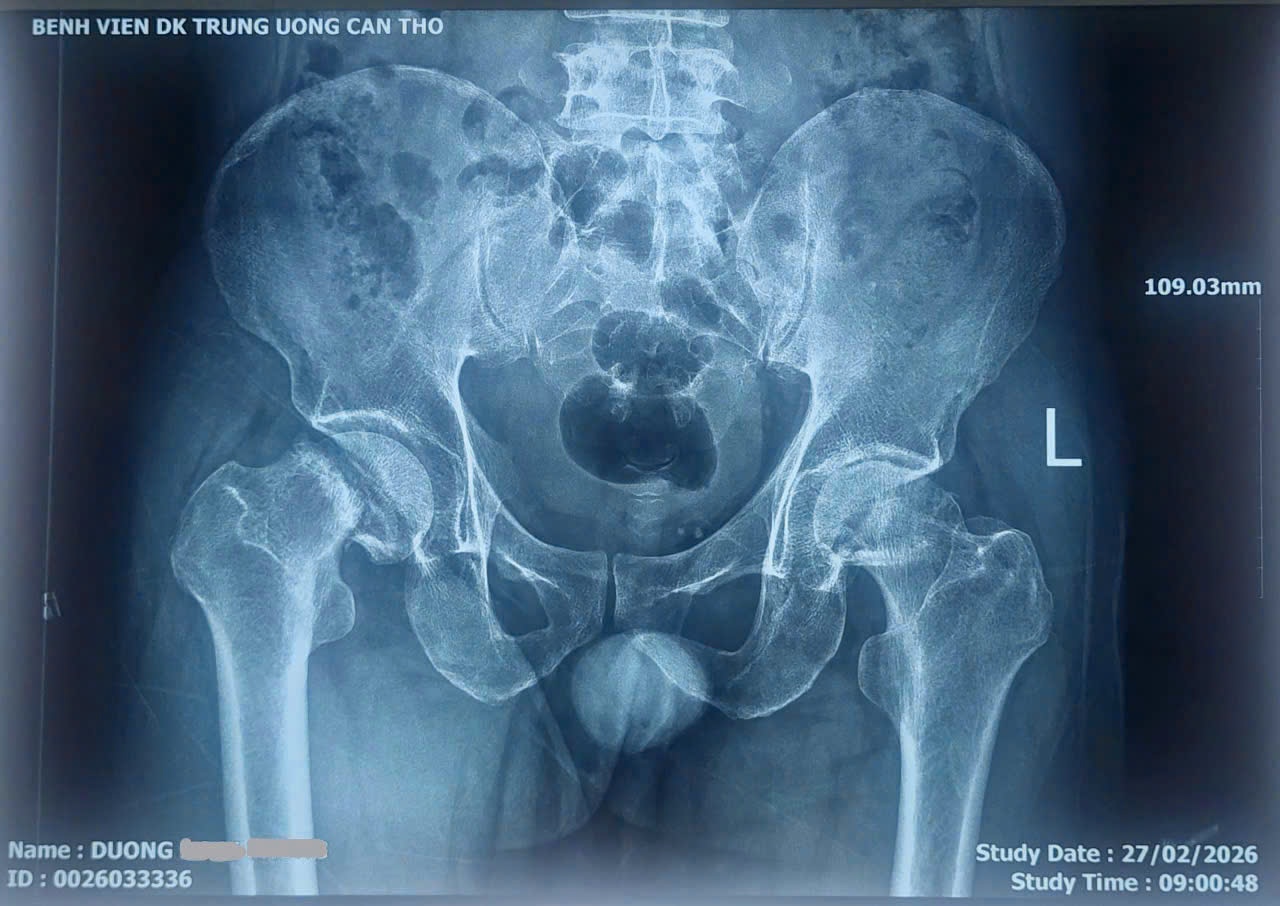

Bệnh nhân Dương H.P. (sinh năm 1977, ngụ thành phố Cần Thơ) nhập viện ngày 28/2/2026 trong tình trạng đau khớp háng hai bên kéo dài nhiều năm, đặc biệt tăng nặng trong khoảng 6 tháng gần đây. Người bệnh thường xuyên phải sử dụng thuốc giảm đau và gặp nhiều khó khăn khi đi lại.

Qua thăm khám lâm sàng và các xét nghiệm hình ảnh, các bác sĩ chẩn đoán bệnh nhân bị hoại tử chỏm xương đùi hai bên một bệnh lý nguy hiểm xảy ra khi nguồn máu nuôi chỏm xương đùi bị giảm hoặc mất hoàn toàn, dẫn đến hoại tử xương, đau kéo dài và có nguy cơ xẹp khớp nếu không được điều trị kịp thời. Bệnh nhân được chỉ định phẫu thuật thay khớp háng.